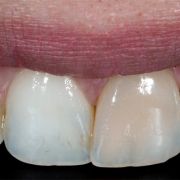

After bleaching, composite is layered (arrow) from inside labially to restore the lost tooth structure from the previous access and to modify the light reflection within the tooth.

The large access cavity decreased in diameter after the inside composite layering at the labial surface.

2- after non vital bleaching, tooth still discolored!

3- after "inside out" composite layering

playing with composite opacities from inside out is very important to treat such a cases !